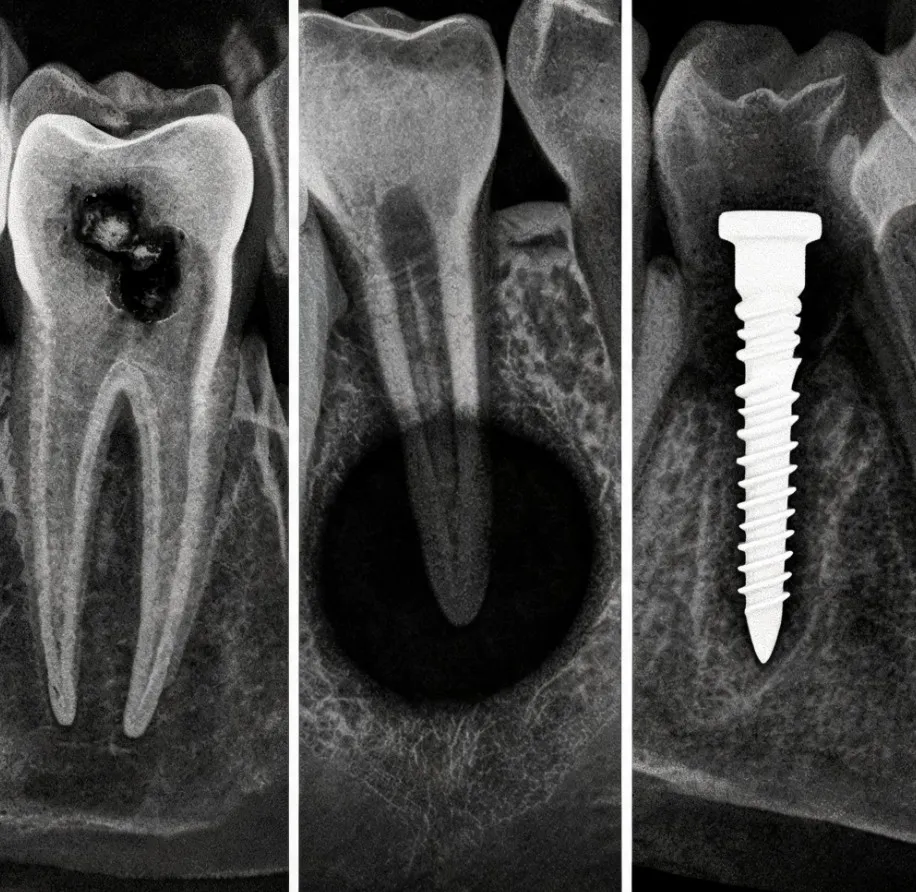

Имплантация: как AI помогает планировать лечение

Имплантация требует особенно точной диагностики. Перед установкой импланта нужно оценить объём и плотность кости, расстояние до нижнечелюстного нерва, гайморовой пазухи, соседних корней и других важных структур. Ошибка на этапе планирования может привести к осложнениям, боли, воспалению, повреждению тканей или нестабильности импланта.

Здесь нейросети могут помогать в нескольких направлениях. Они участвуют в сегментации анатомических структур на КЛКТ, анализируют костную ткань, помогают врачу оценить зону установки и иногда ускоряют подготовку цифрового плана. В сложных случаях это особенно ценно: например, если у пациента давно отсутствует зуб, кость уменьшилась, рядом проходят важные структуры или требуется костная пластика.

Но планирование имплантации нельзя полностью передать алгоритму. Врач учитывает прикус, состояние дёсен, гигиену, общее здоровье, курение, диабет, нагрузку на будущую конструкцию, тип протеза и долгосрочный прогноз. AI может ускорить анализ снимка, но хирургическое решение остаётся клиническим.